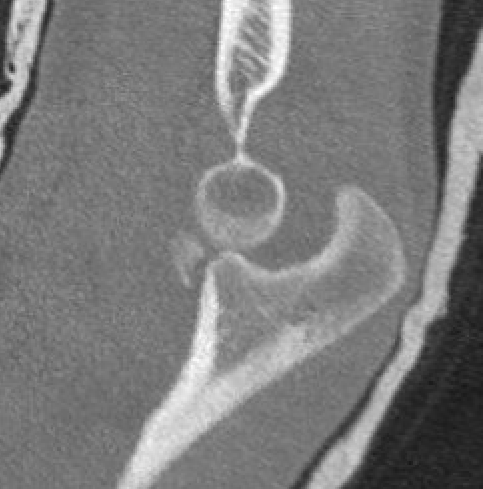

Anteromedial coronoid facet fragment

- associated with varus posteromedial rotational force

- associated with tear of lateral ulna collateral ligament (LUCL)

O'Driscoll classification anteromedial coronoid facet fractures

Type I Type II Type III

Transverse fractures Anteromedial facet fractures Basilar fractures